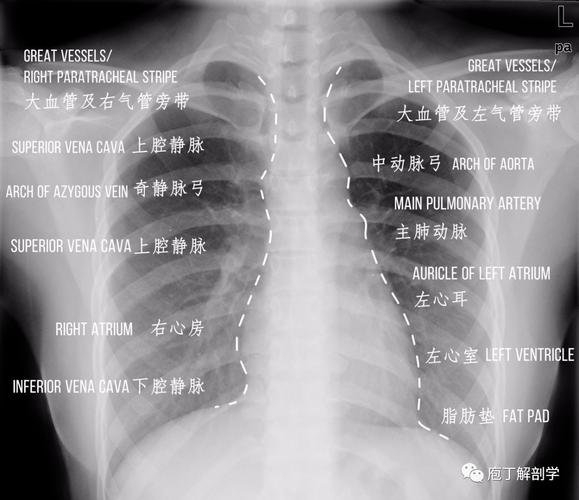

超详细胸片教学 不信你还学不会!

"0"基础小白必备宝典:认识肺部影像结构

正常胸片图片图解

肺部正常胸片影像图片

正常胸片影像图片